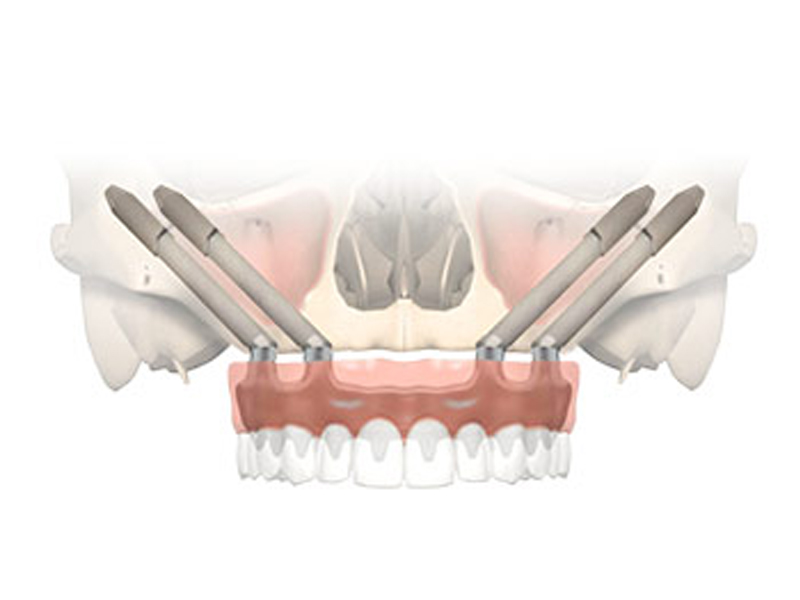

Zygomatic implants

The zygomatic implants are an excellent solution in cases of patients with little jaw bone. In this type of intervention the advantage is to be able to insert an implant without additions or regeneration of jaw bone.

The zygomatic implants also allow patients who do not have a sufficient amount of bone to support a fixed prosthesis and have a stable dentition in a very short time and in total relaxation.

Extreme precision of implant placement

Fast, safe, painless application